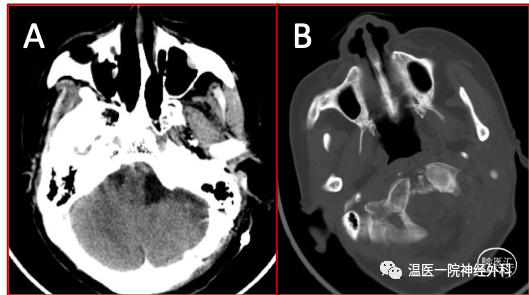

图5 A、术后CT显示瘤腔干净;B、枕髁基本完整保留